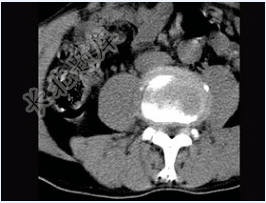

- 单项选择题男,45岁,腰痛,请结合所提供图像,选择最佳答案( )

A、前纵韧带钙化

B、椎间盘膨出

C、椎间盘突出

D、腰椎骨质增生

E、椎间盘未见异常